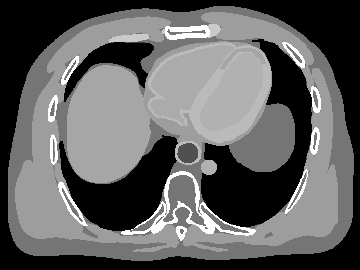

In practice, for sufficiently close to 1, we directly interpret the sequence of ITALE iterates as approximate minimizers of the objective function (2) for penalty parameters along a regularization path. We select the iterate using cross-validation on the prediction error for , and we use the final estimate . Figure 1 compares in simulation using the -regularizer (3) with (globally) minimizing the TV-regularized objective

with selected also using cross-validation. The example depicts a synthetic image of a human chest slice, previously generated by [GHG+17] using the XCAT digital phantom [SSM+10]. The design is an undersampled and reweighted Fourier matrix, using a sampling scheme described in Section 3 and similar to that proposed in [KW14] for TV-regularized compressed sensing. In a low-noise setting, a detailed comparison of the recovered images reveals that provides a sharper reconstruction than . As noise increases, becomes blotchy, while begins to lose finer image details. Quantitative comparisons of recovery error are provided in Section 4.2 and are favorable towards ITALE in lower noise regimes.

Next, we tested ITALE on three 2-D image examples, corresponding to piecewise-constant digital phantom images of varying complexity: the Shepp-Logan digital phantom depicted in Figure 6, a digital brain phantom from [FH94] depicted in Figure 7, and the XCAT chest slice from [GHG+17] as previously depicted in Figure 1.

Each image was normalized to have pixel value in . We sampled random Fourier design matrices as specified in (11), fixing the constant in the weight distribution (10) for this design. This yielded the best recovery across several tested values for both ITALE and TV. The measurement error was generated as Gaussian noise , applied to the measurements before the normalization. Tables 3, 4, and 5 display the RMSE of the estimates and for a single simulation, with tuning parameters selected by 5-fold cross-validation. Best-achieved errors are reported in Appendix C.

For the simpler Logan-Shepp and brain phantom images, which exhibit stronger gradient-sparsity, ITALE yielded lower RMSE in nearly all tested undersampling and signal-to-noise regimes. For the XCAT chest phantom, with undersampling ranging between 15% and 50%, ITALE yielded lower RMSE at a range of tested noise levels, and in particular for those settings of higher signal-to-noise. With 10% undersampling for the XCAT phantom, ITALE was not able to recover some details of the XCAT image even with no measurement noise, and RMSE was higher than TV at all tested noise levels. Results of Appendix C indicate that this is partially due to sub-optimal selection of the tuning parameter using 5-fold cross-validation, caused by the further reduction of undersampling from 10% to 8% in the size of the training data in each fold.

Examples of recovered signals and are depicted for the Shepp-Logan and brain phantoms in Figures 6 and 7, at 15% and 20% undersampling for two low-noise and medium-noise settings. The qualitative comparisons are similar to those in the 1-D simulations, and to those previously depicted for the XCAT chest slice in Figure 1: As measurement noise increases, ITALE begins to lose finer details, while TV begins to yield an undersmoothed and blotchy image. These observations are also similar to previous comparisons that have been made for algorithms oriented towards versus TV regularization for direct measurements , in [XLXJ11, FG18, KG19].